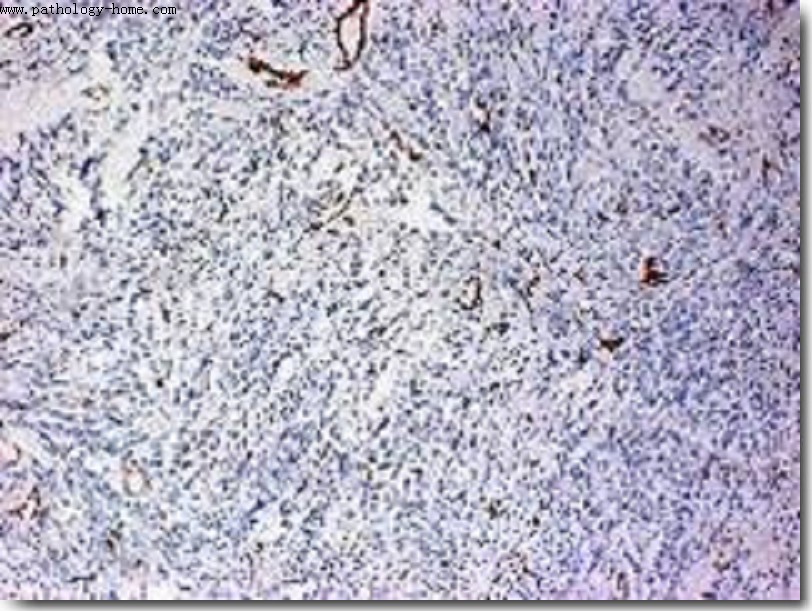

6.病理检测:HE染色、特殊染色、组织切片、免疫组化、流式细胞分选

免疫组化IHC